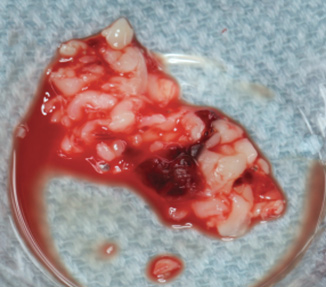

Fig 1. Typical PRF membranes obtained after centrifugation and cut into small PRF fragments.

Figure 1

Fig 2. PRF after being cut into ~1-mm sized fragments.

Figure 2

The biological advantages of using PRF for sinus augmentation procedures have been well-documented.14 PRF serves as a scaffold capable of protecting the Schneiderian membrane, may be combined with bone grafting materials to improve their handling and stability, and has been shown to increase new blood flow to the poorly vascularized area of the sinus cavity (Figure 1 through Figure 3). As a result, PRF is commonly used for all sinus augmentation procedures. The size of the sinus cavity has been the primary deciding factor for when to use PRF alone versus combined with a bone grafting material.